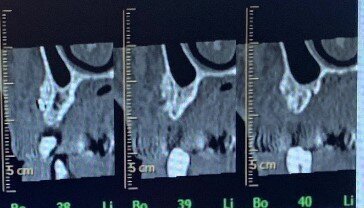

In seguito all’intervento di rialzo di seno mascellare con contestuale GBR è stata eseguita la radiografia ortopanoramica che mostra il corretto riempimento dell’area atrofica del seno mascellare con granuli cortico-spongiosi di osso di origine bovina. Al controllo dopo tre settimane i tessuti molli dell’area trattata risultano perfettamente guariti. La TC Dentalscan effettuata dopo 6 mesi per il controllo della zona rigenerata evidenzia la perfetta guarigione della zona con aumento dello spessore osseo di 5 mm e dell’altezza ossea di 11 mm.

L'evoluzione della tecnica chirurgica nell’approccio attraverso finestra laterale all’osso mascellare per il sollevamento della membrana del seno, ha lo scopo di ridurre le complicanze che possono compromettere l’esito dell’intervento e la sopravvivenza dell’impianto. La chirurgia piezoelettrica ha dimostrato il vantaggio di ridurre drasticamente il tasso di perforazione, aumentando così la percentuale di successo complessivo della tecnica di rialzo di seno mascellare15 (Figg. 19-22).